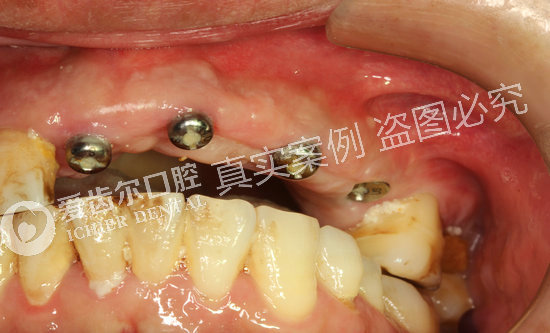

安装愈合基台

用永久基台换下愈合基台